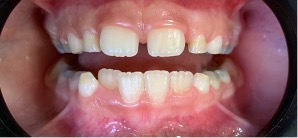

En 2015, cuando el paciente tenía 3 años y 8 meses, la madre fue en busca de explicaciones para dichas alteraciones. En la anamnesis fue relatado que los primeros dientes primarios erupcionaron alrededor de los 12 meses de edad y que la madre notó alteración del color desde el inicio, pero como la pediatra la había alertado sobre la alteración de color, no buscó rápida atención. Durante el examen clínico se observó coloración verde en todos los dientes prmarios presentes; la pigmentación se localizaba en los incisivos centrales y laterales superiores e inferiores en toda extensión de la corona hasta el tercio cervical. En los caninos inferiores la coloración verde se extendió desde el borde incisal al tercio medio de la corona. Los primeros y segundos molares inferiores y superiores estaban afectados en casi toda la extensión de la corona por un tono verde oscuro, y apenas el tercio cervical no presentaba coloración (Figuras 1 y 2). Los dientes primarios presentaron una morfología normal (esmaltes con superficies lisas y regulares), buenas condiciones de higiene bucal (bajo índice de placa dental) y ausencia de manchas blancas, lesiones de caries y de hipoplasias y movilidades. Los tejidos blandos estaban íntegros y presentaban coloración normal. En las radiografías no se observó ninguna alteración (Figura 3).

Figura 1: Imagen vestibular de los dientes. Se observa pigmentación verde en la dentición. (A) Frontal y (B) Lateral izquierda. Paciente con edad de 3 años y 8 meses.